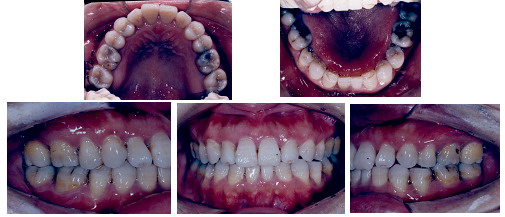

以下是一名38岁女性反合患者的病例,治疗前存在前牙反合、牙弓形态异常、牙弓左右不对称同时伴有颜面骨骼发育异常,面部比例失调,唇突度不协调以及全口不同程度的牙周炎症牙槽骨丧失、上颌尖牙早失,治疗难度很大。经过牙周和正畸的共同努力,在控制牙周炎症之后拔除两颗下切牙,采用目前国际上最流行的MBT矫治技术,经过15个月的治疗,达到了理想的治疗效果。

治疗完成